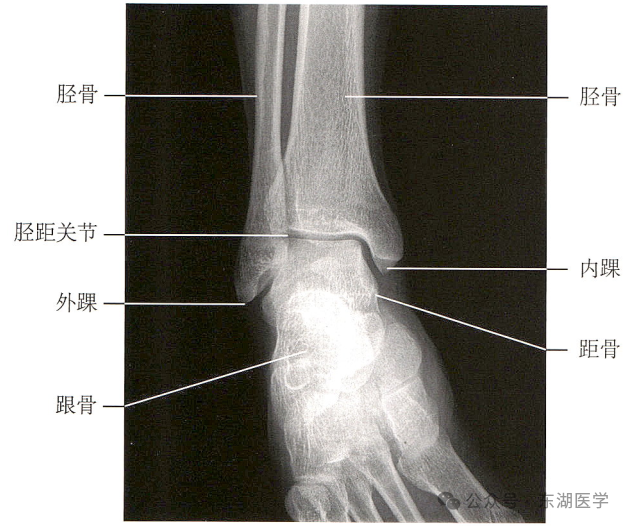

足以骨骼为支架,包括7块跗骨、5块跖骨、14块趾骨,彼此间借关节和韧带相连接。